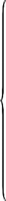

112Rhinosporidium kinealyi, portion of ripe cyst. (After Minchin and Fantham)197